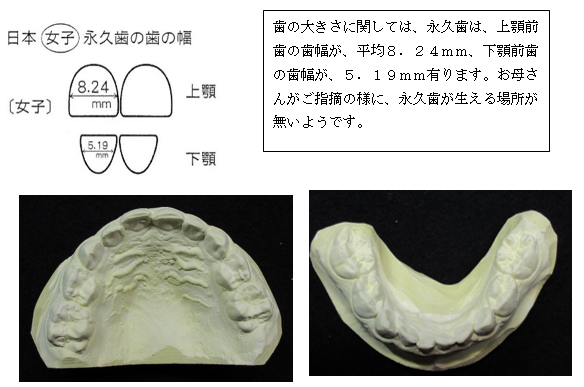

主訴)①乳歯の状態で、下顎前歯が重なっている。永久歯の生える場所が無いので心配です。

診断名:上下顎前歯部叢生を伴う乳歯列過蓋咬合です。

(模型所見)

歯の大きさ(歯幅mm)